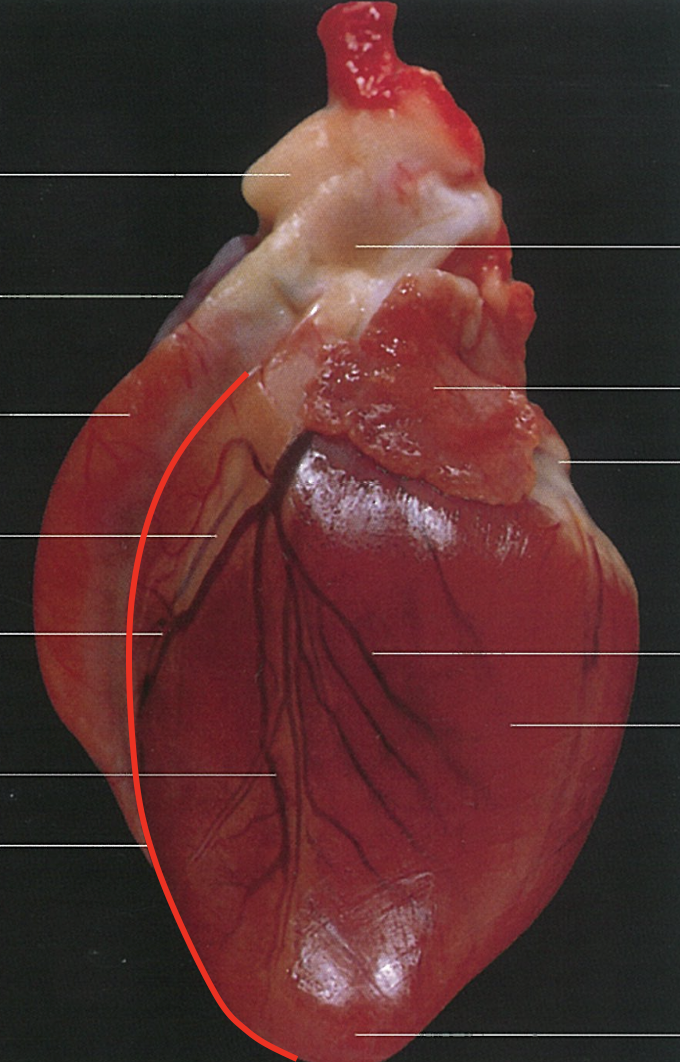

Name the Surface.

Auricular Surface

Apex

Paraconal Interventricular Groove